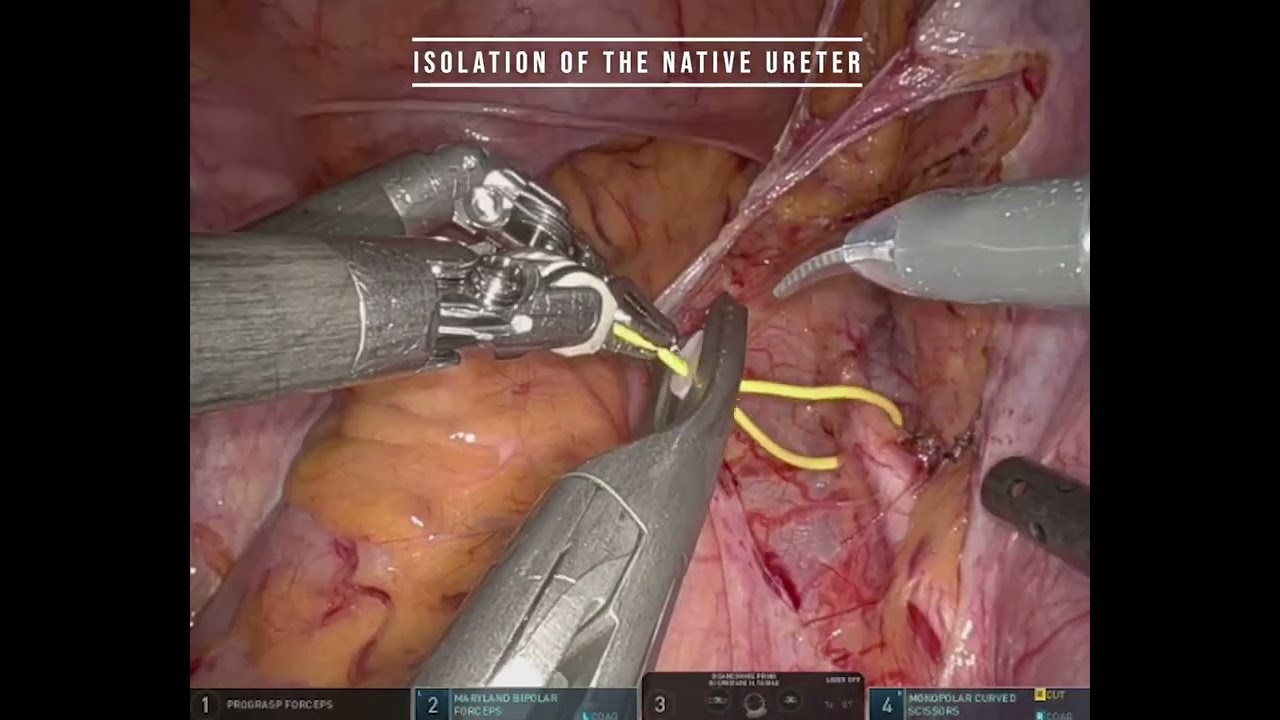

#358 R. A. Radical Cystectomy with Intracorporeal modified Pitcher-pot neobladder- Dr. Sumit Agrawal

KS Awards, Robotics, Surgeon ';